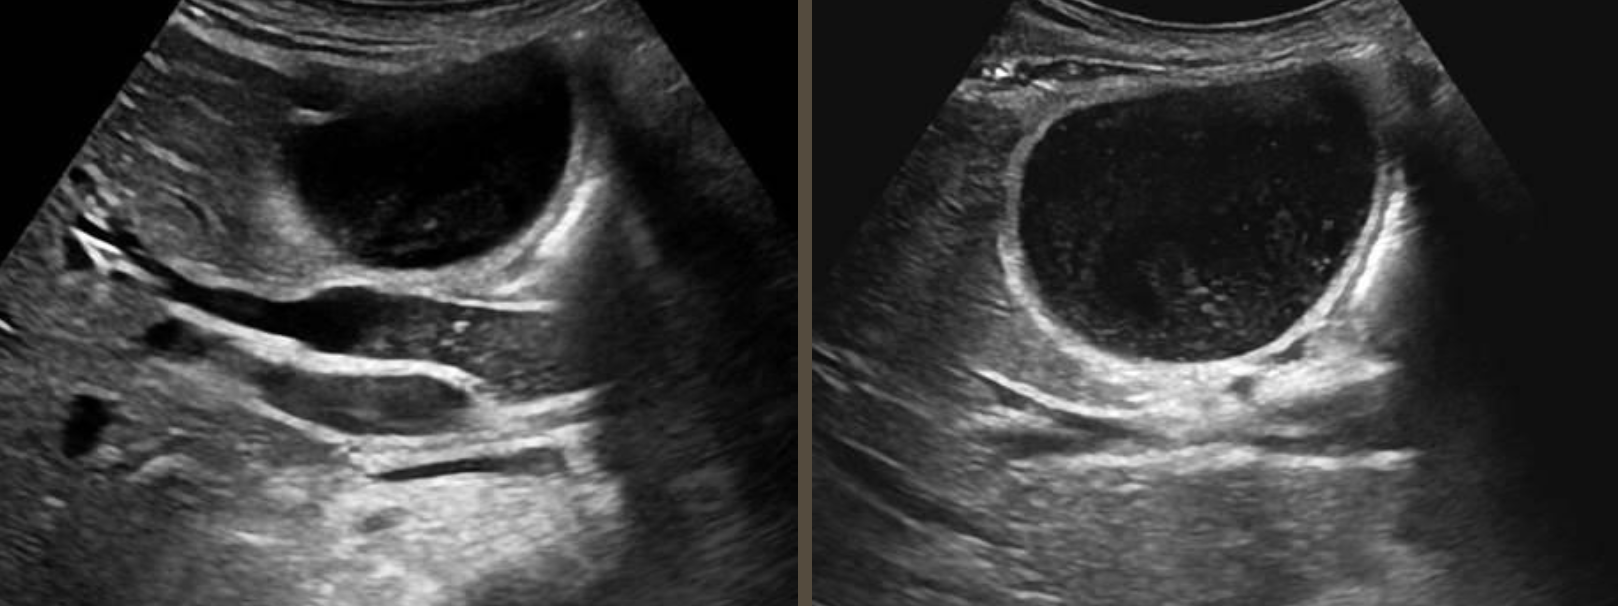

Simple Renal Cyst → common lesion of kidney, fluid-filled sac (benign, Bozniak 1)

2D US: anechoic, well-defined smooth, thin wall, round or ovoid, posterior enhancement

color doppler: avascular

DDX: complex cyst

Complex Renal Cyst → any cyst that is not a simple cyst

2D US: well-defined cystic structure, internal echoes or anechoic, septations, focal hypoechoic inner mural extension, can be hemorrhagic

color doppler: if solid can have vascularity

DDX: malignant tumor, RCC